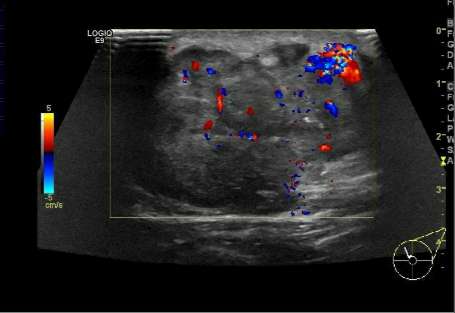

7.乳腺结节的血供。

良性病变多是无血供的实性结节,而恶性结节由于对营养成分的过量摄取,往往其周围的血管数目、血供丰富,往最高血流速度大于20cm/s,血流阻力指数RI≥0.7,这是恶性结节的特征性表现。

乳腺恶性肿瘤彩超表现,乳腺结节良性恶性彩超对照图

结节内血供丰富,是恶性的征象。